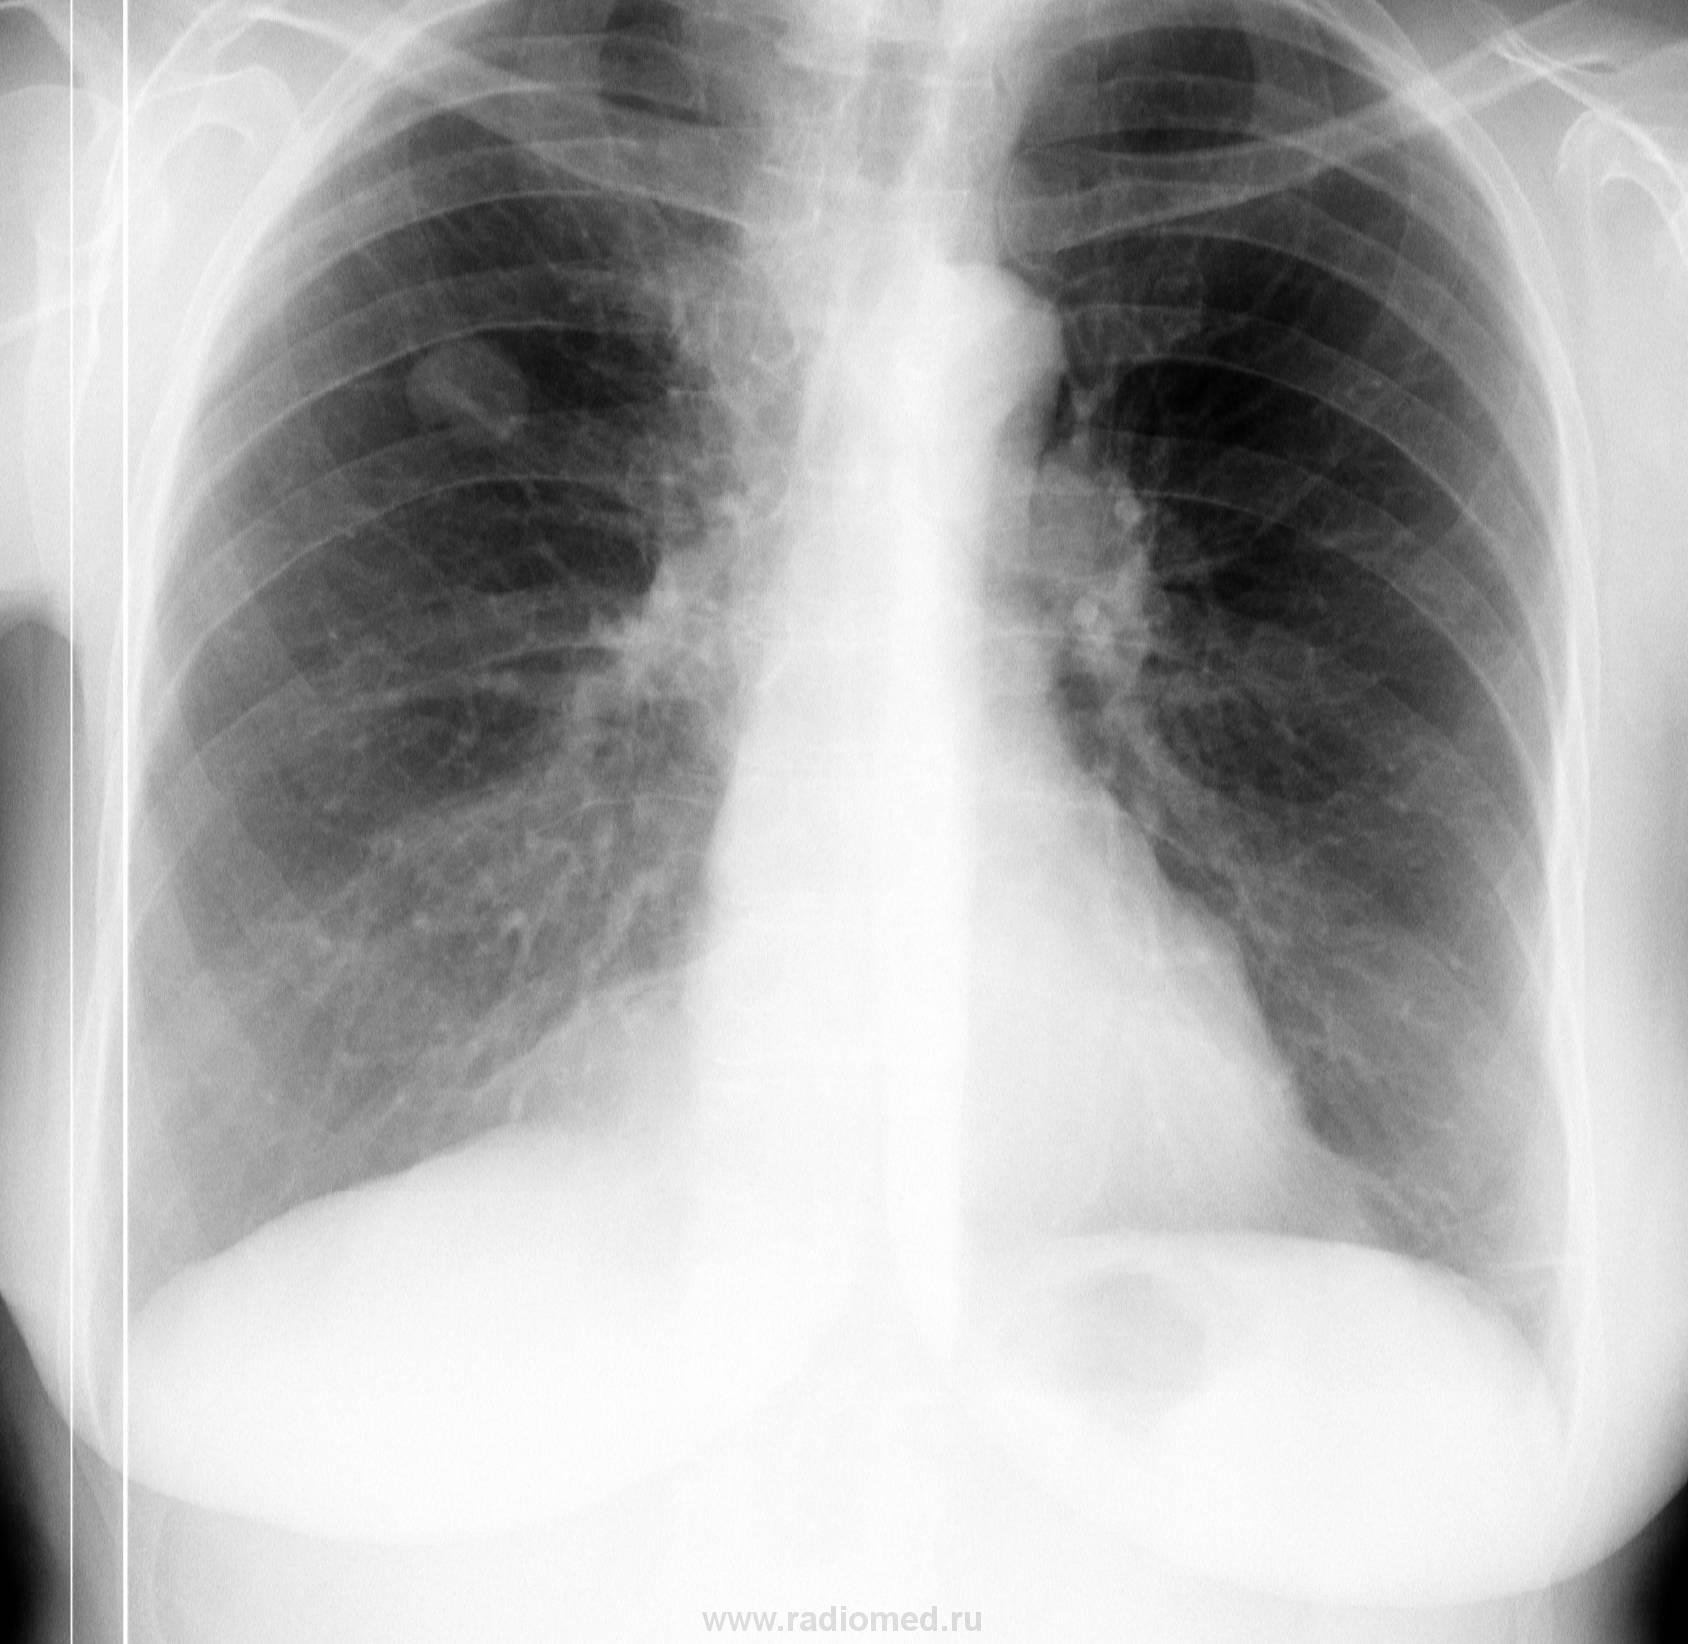

Женщина. Из другой страны. У родственников в гостях. Решила пройти ФГ. Что скажете, коллеги?

Новообразование на коже спины, на короткой ножке, внешне не изменено, некоторое покраснение кожи вокруг.

Гомогенность и четкость при полной индиферентности окружающей легочной ткани говорит о доброкачественности, так что опытного рентгенолога на мякине не проведешь, даже без бокового. Но при желании попить финансов с пациента можно крутить на КТ, МРТ и т.д., лишь бы бабок хватило.

А, как ресценили снижение прозрачности легочной ткани, помеченное стрелочками уважаемый Виктор Григорьевич?

Случайно не липома кардио-диафрагмального угла?

Расценил, как целомическую кисту перикарда...а как мы ее от липомы отдифференцируем в данном случае, только по этим снимкам?

Это – липома, целомическая киста перикарда должна быть плотнее, да и контур диафрагмы здесь размыт, ИМХО.

Согласен с Петровичем - липома это.